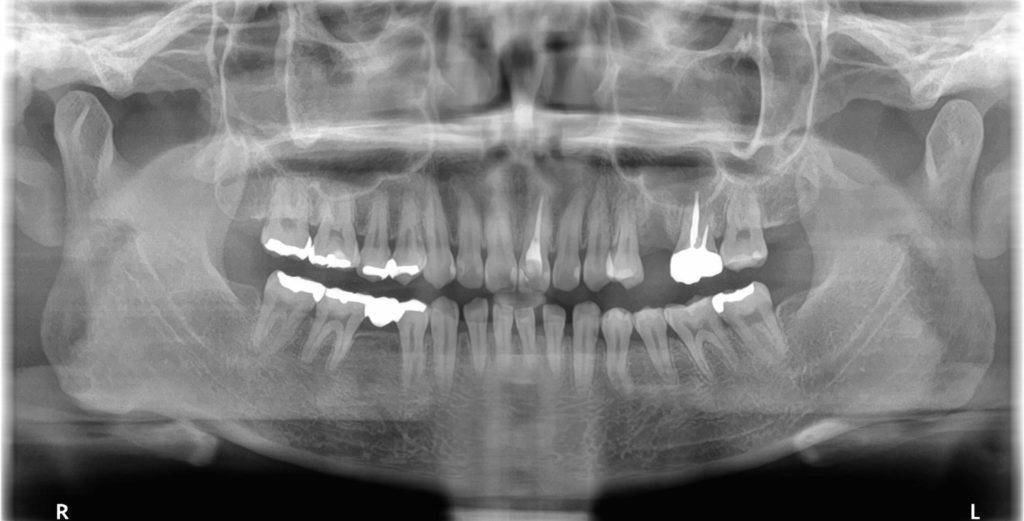

初診時の様子

はい。3ヶ月前に左上の歯を抜いたのですが、ブリッジにするかインプラントにするかで迷っています。

抜歯をした箇所が笑うと見えてしまうので、なるべく早く治療をしたいと考えています。

インプラントは精密な治療なので、しっかり診査・診断を行い、最適な治療計画をご提案させていただきます。